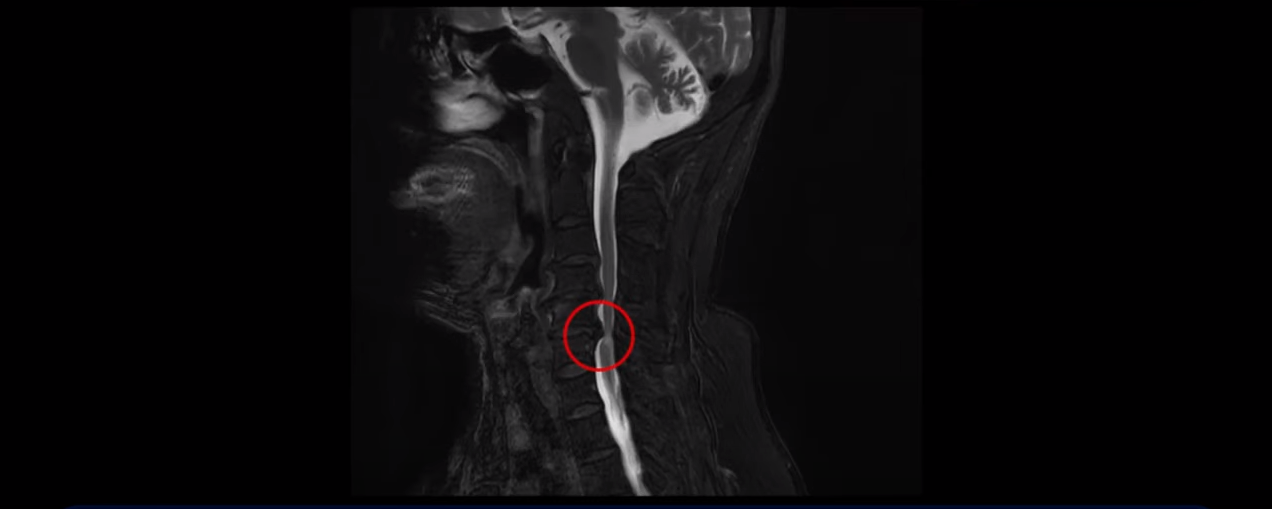

이 환자분은 목디스크 5, 6번에 심한 디스크로 인해 경추척수증이 발생한 환자입니다. 심하게 밀려 나온 디스크로 인해 척수신경이 눌려 신경손상이 하얗게 보입니다.

이 환자분의 증상은 양손바닥에 다 마비가 오고 다리에 힘이 빠지면서 균형을 못 잡고 비틀대면서 잘 걷지 못하는 상태였는데, 이는 전형적인 경추척수증의 증상이죠. 대학병원에서 별다른 자세한 설명 없이 무조건 수술해야 된다는 말에 저희 모커리한방병원에 내원하셨습니다.